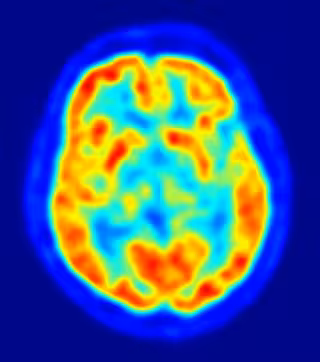

Las áreas del cerebro afectadas por la enfermedad de Alzheimer podrían comenzar a reducirse hasta una década antes de que se diagnosticara la demencia, según un estudio de la Escuela de Medicina de Harvard en Boston (Estados Unidos) que se publica en la revista 'Neurology'.

En su estudio, los investigadores utilizaron escáneres de imágenes de resonancia magnética para medir las áreas del cerebro en las personas sin problemas de memoria u otros signos de Alzheimer, después les siguieron durante años para ver quienes desarrollaban la enfermedad.

Los investigadores se centraron específicamente en las medidas de áreas conocidas por su participación en la enfermedad de Alzheimer. Aquellos con un menor tamaño cerebral en las áreas asociadas a la enfermedad eran mucho más propensos a desarrollar la enfermedad que aquellos con las medidas de mayor tamaño.